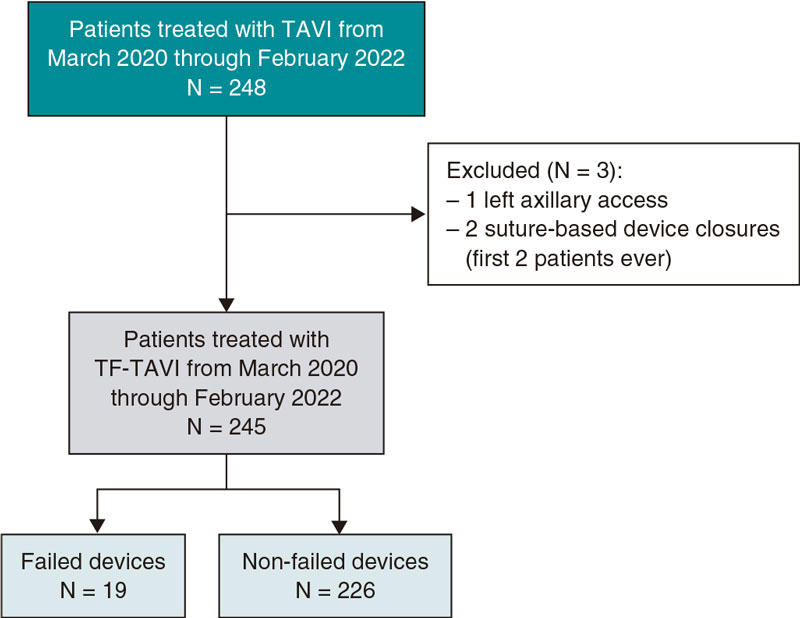

Ectasia and great proximal-distal diameter mistmatch at the lesion were the main indication for the use of this stent, in 72.6% of the lesions, with a mean vessel reference diameter of 4.1 mm ± 0.8 mm. A certain size was required to use this type of stent. The percutaneous coronary interventional on a bifurcation was the second most common indication, in 27.4% of the patients (2 of them on the LMCA). The most common type of bifurcation according to the Medina classification was 1-1-0, in 9 cases (52.9%). The secondary branch was damaged in 17% of the patients. The provisional stenting technique was the most widely used in 15 cases (88.2% of bifurcations) re-crossing to the secondary branch in 9 of them (60%). The dilatation of the secondary branch only occurred in 7 patients and only in the other 2 stents were implanted: one in a 0-1-1 bifurcation according to the Medina classification (minicrash technique) and the other in a 1-1-1 bifurcation according to this classification (TAP technique [T-and protrusion technique]). In both cases the STENTYS Xposition S stent was implanted in the main vessel and a non-self-apposing stent in the secondary branch (figure 1).

Figure 1. A: lesion with significant thrombotic load in the mid right coronary artery, which remains after thrombus aspiration. B: 3.5-4.5 mm × 27 mm Xposition S direct stent implantation. C: final angiographic result. D: significant stenosis in distal left main coronary artery. E: 3-3.5 mm × 27 mm Xposition S stent implantation from the proximal left main coronary artery to the left anterior descending coronary artery. F: angiographic result after postdilatation.